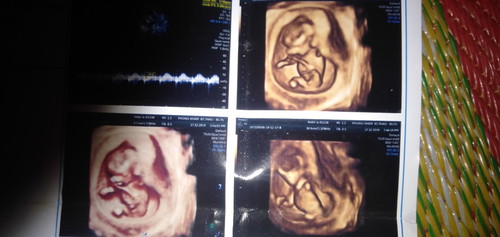

mấy mom có nhìn ra trai hay gái ko ạ?

Cho e câu trả lời với

Hình như có chim non 😂 mom ơi, mom cho bé nhà mình 1like nhé, mình cảm ơn https://community.theasianparent.com/booth/809838?d=android&ct=b&share=true

Hình như có chim non kìa m😂😂

Hình như là bé trai